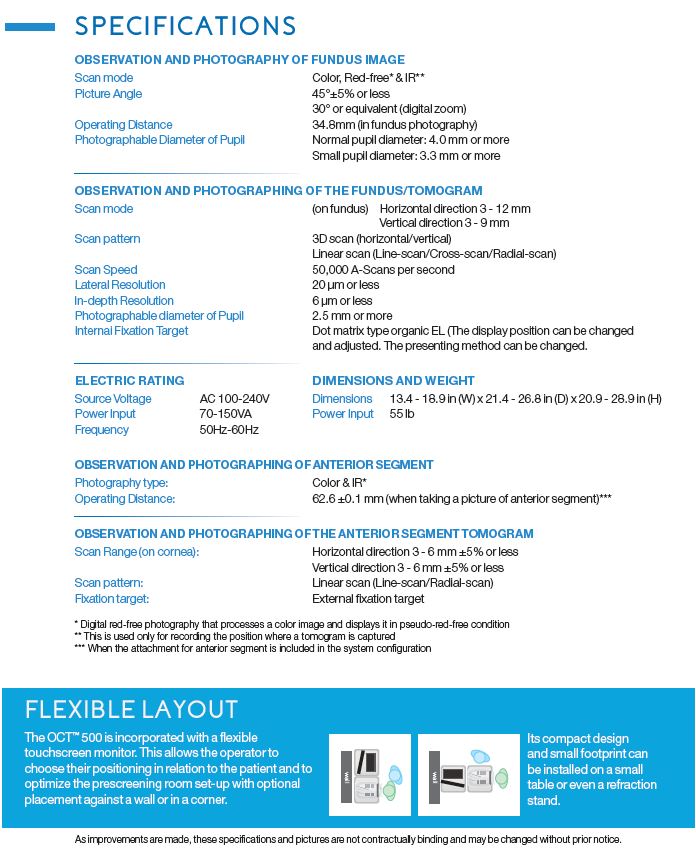

MORE DETAILS IN LESS TIME

A scanning speed of 50,000 A-scans/sec allows for faster tomography acquisition and produces clear, high-definition cross-sectional retinal images through a simple interface.

The 12mm x 9mm wide field OCT scan for the optic nerve and macula provides a fast screening and clear overview in a single image.

OCT 500 is the most user-friendly OCT on the market due to its fully automated function. With one touch on the screen, eye focus, optimization, and image capture are performed automatically. After capturing, the report can be displayed immediately by clicking on a single icon.

Semi-automatic or manual mode is available to help adjust the alignment and scanning position for patients. A variety of functions are available and easily accessed on the touchscreen monitor.

Live Fundus View (OCT-LFV) is a tool to enable image capture through smaller pupils down to a diameter of 2.5mm.